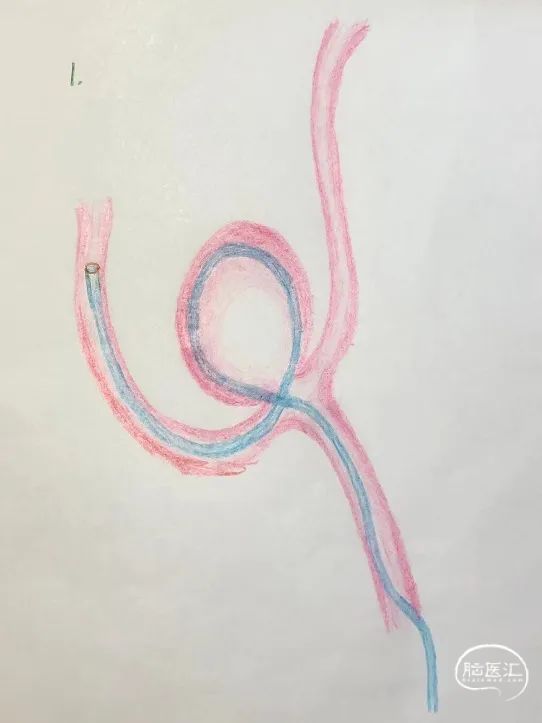

将预塑形的45°微导管输送至对侧大脑前动脉远端时,微导丝超选困难,最终导丝在动脉瘤瘤腔内成袢进入对侧大脑前动脉,微导管遂成袢通过动脉瘤置于对侧A2段。微导丝调整无法使微导管解袢,鉴于Atlas支架具备优异的顺应性,术中尝试性释放支架前端进行锚定,再回拉微导管解袢,最终安全释放支架。

对侧支架锚定解袢过程示意图。